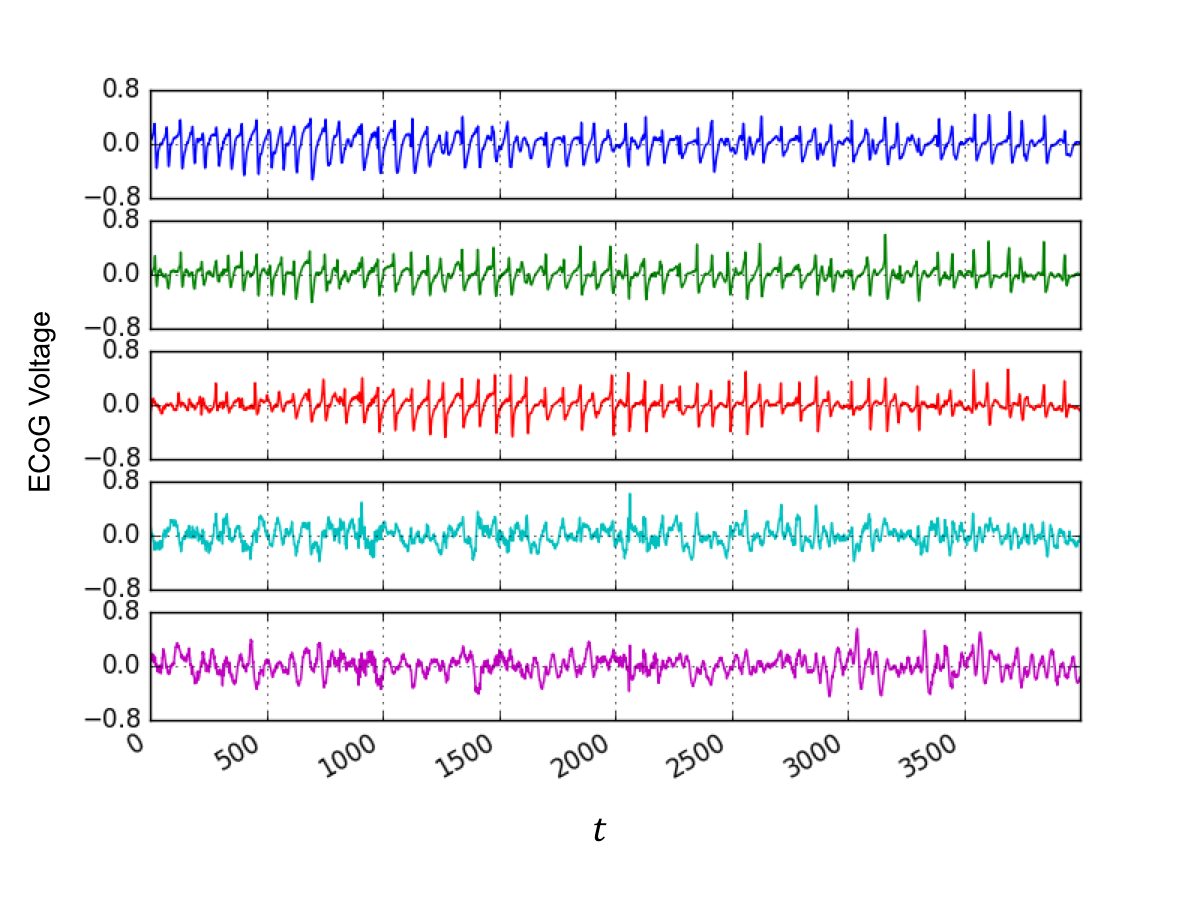

VI-A Seizure data description

Seizure data were obtained for a -year-old female subject with a case of intractable epilepsy at the University of California, San Francisco (UCSF) Epilepsy Center; see also [26]. An subdural electrode grid was implanted into the cortical surface of the subject’s brain, and two accompanying electrode strips, each comprising six electrodes (a.k.a., depth electrodes) were implanted deeper into the brain. Over a period of five days, the combined electrode network recorded ECoG time series, consisting of voltage levels measured in a region within close proximity of each electrode.

ECoG epochs containing eight seizures were extracted from the record and analyzed by a specialist. The time series at each electrode were first passed through a bandpass filter, with cut-off frequencies of and Hz, and the so-termed ictal onset of each seizure was identified as follows. A board-certified neurophysiologist identified the initial manifestation of rhythmic high-frequency, low-voltage focal activity, which characterizes the onset of a seizure. Samples of data before and after this seizure onset were then extracted from the ECoG time series. The per-electrode time series were then divided into s windows, with s overlaps between consecutive windows, and the average spectral power between Hz and Hz was computed per window. Finally, power spectra over all electrodes were averaged, and the ictal onset was identified by visual inspection of a dramatic increase in the average power. Two temporal intervals of interest were picked for further analysis, namely, the preictal and ictal intervals. The preictal interval is defined as a s interval preceding seizure onset, while the ictal interval comprises the s immediately afterwards. Further details about data acquisition and pre-processing are provided in [26].